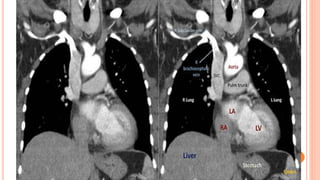

(2) CT

CT at level of Aortic Arch

CT at level of Carina

CT at levelof Aortic Arch

• 38.

CT at levelof Carina